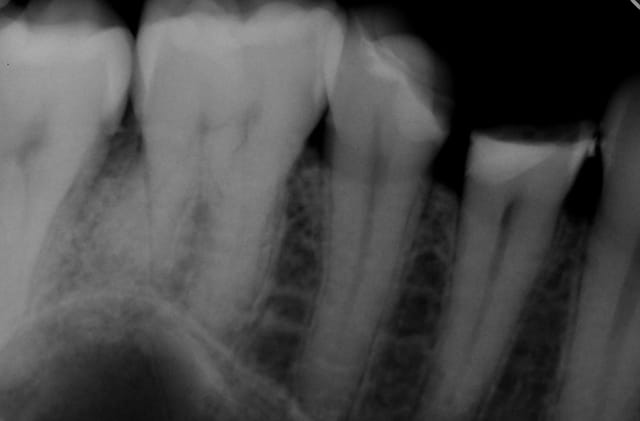

Alors comment traiteriez vous cette 24 asymptotique, qui présente un enorme délabrement sous gingival , notez que l'émail n'est plus soutenu par la dentine à aucun endroit ?

> Alors comment traiteriez vous cette 24 asymptotique, qui présente un enorme

> délabrement sous gingival , notez que l'émail n'est plus soutenu par la dentine

> à aucun endroit ?

1ère séance remontées de la marche distale au compo flow + compo de restauration / réalisation d'un IDS , le tout sous digue bien sur (voir radio jointe , désolé à l'envers))